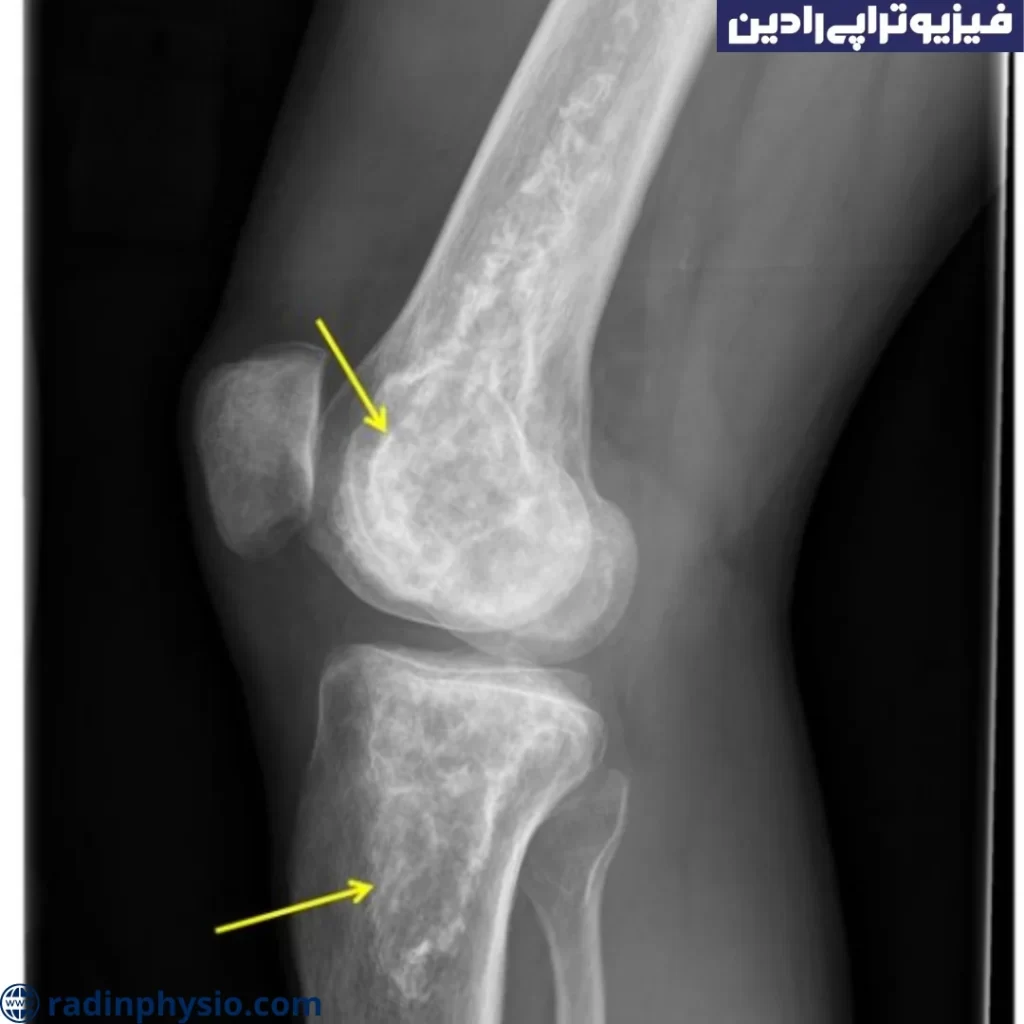

- ● تصویربرداری: برای تشخیص استئونکروز زانو، تصاویر تشخیصی مانند ایکسری زانو و یا MRI استخوان ممکن است درخواست شود. این تصاویر ممکن است نشان دهند که استخوان زانو تخریب شده است و علائم استئونکروز را نشان دهند.